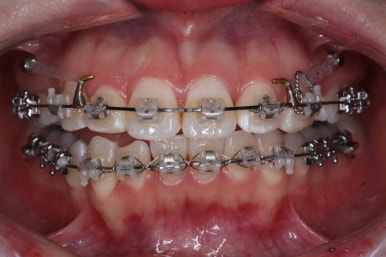

윗니는 발치를 했고, 잇몸뼈에 미니스크류를 식립하여 앞니를 뒤로 당겨넣고 있습니다.

아랫니는 아직 덜 가지런해졌네요.

이 뽑은 자리가 점점 줄어드는 것이 보입니다.

아랫니도 많이 가지런해졌네요.

이 뽑은 자리가 반 이상 줄어든 것 같네요. 아랫니는 마무리를 해도 될 정도로 많이 좋아졌습니다.